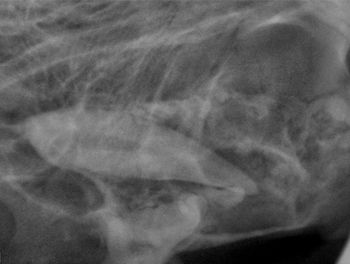

Chronicling the progression of periodontal bone destruction resulting in mandibular fractures in a dog.